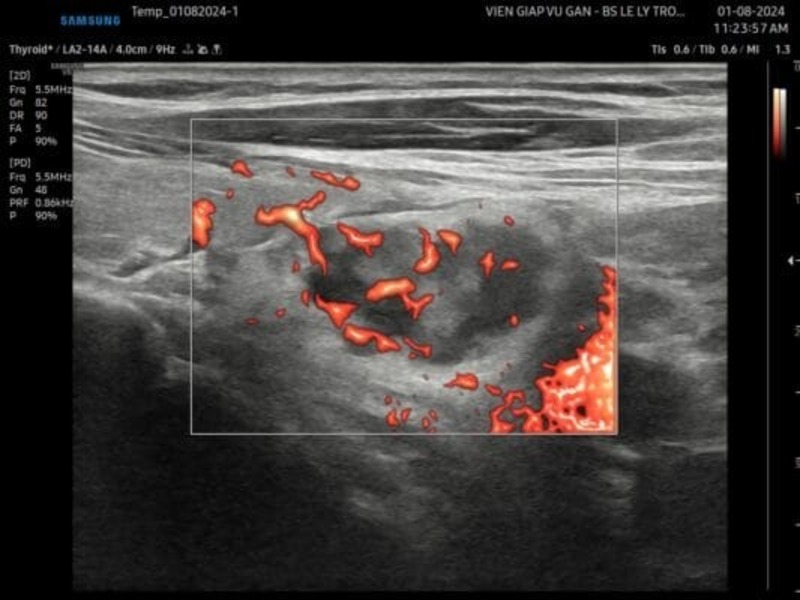

SIÊU ÂM: Vị trí cạnh trái khí quản, ngay cực dưới tuyến giáp có khối đặc, echo kém không đồng nhất, xen lẫn các vùng echo dày, viền echo dày, bờ đều, giới hạn rõ, kích thước khoảng 22x15x15mm. Siêu âm doppler ghi nhận mạch máu phân bố từ cực trên phân nhánh vào trong và ngoại vi bướu.

Kết luận: Tổn thương cạnh trái khí quản nghĩ bướu tuyến của tuyến cận giáp.

Bướu tuyến cận giáp có xu hướng giảm âm đồng nhất so với tuyến giáp phía trên. Tuy nhiên trường hợp này bướu có hồi âm không đồng nhất kèm viền echo dày xung quanh, đây là hình thái ít gặp.